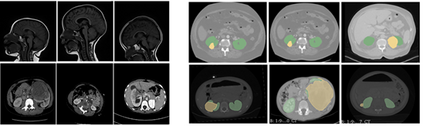

Due to a high heterogeneity in pose and size and to a limited number of available data, segmentation of pediatric images is challenging for deep learning methods. In this work, we propose a new CNN architecture that is pose and scale invariant thanks to the use of Spatial Transformer Network (STN). Our architecture is composed of three sequential modules that are estimated together during training: (i) a regression module to estimate a similarity matrix to normalize the input image to a reference one; (ii) a differentiable module to find the region of interest to segment; (iii) a segmentation module, based on the popular UNet architecture, to delineate the object. Unlike the original UNet, which strives to learn a complex mapping, including pose and scale variations, from a finite training dataset, our segmentation module learns a simpler mapping focusing on images with normalized pose and size. Furthermore, the use of an automatic bounding box detection through STN allows saving time and especially memory, while keeping similar performance. We test the proposed method in kidney and renal tumor segmentation on abdominal pediatric CT scanners. Results indicate that the estimated STN homogenization of size and pose accelerates the segmentation (25h), compared to standard data-augmentation (33h), while obtaining a similar quality for the kidney (88.01\% of Dice score) and improving the renal tumor delineation (from 85.52\% to 87.12\%).